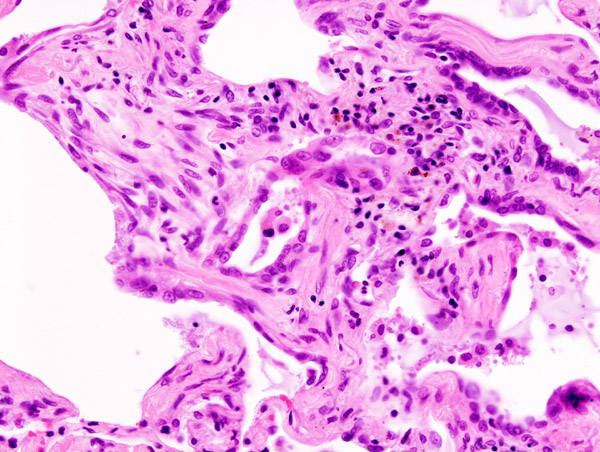

Os monocitos transformam-se em macrófagos que fagocitam as

LDL oxidadas, transformando-se em células

esponjosas que ao se depositarem na íntima origina as estrias gordas, lesão

inicial da ateroesclerose